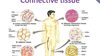

Connective tissue is comprised of a gel-like substance, fibers, and few cells

The gingival connective tissue is comprised of a gel-like substance,

protein fibers, and cells.

Which of the following tissues fills the spaces between the tissues and organs of the body?

B. Connective tissue

B. Connective tissue